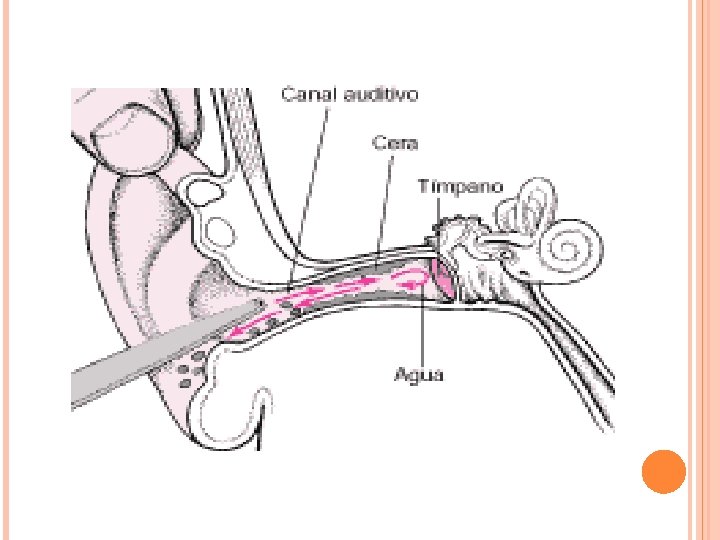

Tapones de cerumen La cera que segregan las glándulas ceruminosas es beneficiosa para la piel del CAE, actúa manteniendo el p. H y produce una película que ayuda a proteger el oído externo de infecciones. Por ello no es adecuada una limpieza excesiva del CAE, solamente en el caso de una producción excesiva y la formación de un tapón se debe eliminar. La cera del oído (cerumen) puede obstruir el canal auditivo y causar picor, dolor y una pérdida de la audición temporal. Eliminar la cera lavando suavemente el canal con agua caliente (irrigación). En caso de tímpano perforado no se utiliza el lavado , se elimina con un instrumento sin punta, un instrumento con un extremo curvado o un dispositivo de vacío.

Cuerpos extraños Los niños pueden llegar a colocarse toda clase de objetos extraños en el canal auditivo, particularmente bolitas, gomas de borrar y semillas. Se extrae con una especie de gancho sin punta. Los objetos son difíciles de sacar debido al riesgo de lesionar el tímpano. Pueden ser extraídas mediante irrigación, pero el agua hace que algunos objetos, como las semillas, se hinchen, volviendo así más difícil su extracción. Cuando el niño no coopera o la extracción resulta particularmente difícil se usa anestesia general. Cuando insectos entran en el canal auditivo. Llenar el canal con aceite mineral mata al insecto y el alivio es inmediato, al mismo tiempo que facilita su extracción.